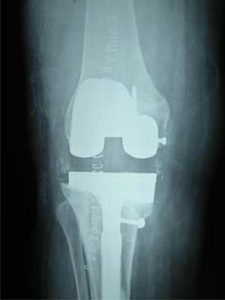

When an Artificial Knee Joint fails, a second operation is required to replace the failing joint. This procedure is called a Revision Joint Replacement.

Mechanical loosening means that the attachment between the artificial joint and the bone becomes loose due to some reason (other than infection). Loosening can occur after a period of extensive use of the joint. This could be as much as 10 to 15 years. This is one reason that surgeons like to wait until absolutely necessary to put in an artificial joint. The younger you are when an artificial joint is put in, the more likely it is that the joint will loosen and require a revision.

If the artificial joint gets infected, it has to be removed to cure the infection. Once the infection settles down a Revision Total Knee Replacement Surgery is done for the patient. Till the time the new implant is put, a cement spacer impregnated with antibiotic is put inside the Knee to give it stability.

If the infection does not come under control, a new implant cannot be inserted and hence fusion of the Knee is the only option.

A fracture may occur near an artificial joint. It is sometimes necessary to use a new artificial joint to fix the fracture. For example, if the femur (thighbone) breaks where the prosthesis attaches, it may be easier to replace the femoral part of the artificial joint with a new piece that has a longer stem that can hold the fracture together while it heals. This is similar to fixing the fracture with a metal rod.

It is not uncommon for the Knee Joint to be either too tight or too loose. If the Knee Joint is too loose, it can cause unsteadiness and pain. If the joint is too tight, the Knee is usually painful and doesn't have a good range of motion. In situations like these a revision becomes necessary.

With the rise in Knee Joint Replacements, surgeons have begun to see wear in the plastic parts of the artificial joints. In some cases, if the wear is discovered in time, the revision may only require changing the plastic part of the artificial joint. If the wear continues until the metal is rubbing on metal, the whole joint may need to be replaced.

Finally, the metal of the artificial joint can break due to the constant stress that the artificial joint undergoes every day. In weight-bearing joints like the Knee, this is greatly affected by how much you weigh and how active you are.